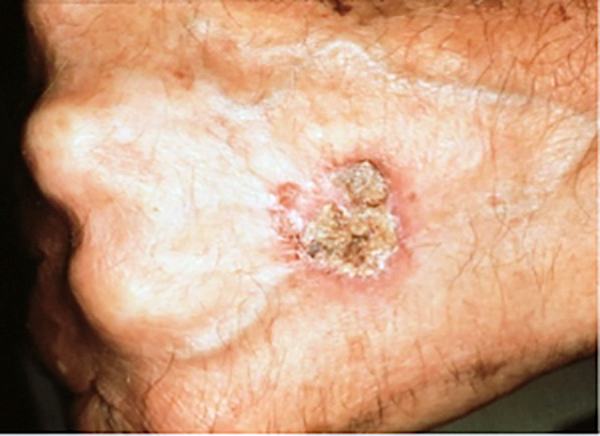

Squamous Cell Carcinoma (SCC) Photos

An elevated growth with a central depression that occasionally bleeds. It may rapidly increase in size. (SCC)

Squamous Cell Carcinoma (SCC) Case Study

A Large Squamous Cell Carcinoma

Deborah S. Sarnoff, MD

Before being admitted to an assisted living facility, an elderly widow was required to have a thorough physical. The doctor (and her adult children who had not seen her undressed in years), were shocked to see a large, raised open wound on her left shoulder and back. For years, she had been covering it and hiding it under clothes. She didn’t want to rock the boat or make a fuss. The lesion (top photo) turned out to be a large SCC, the second most common type of skin cancer. The tumor required extensive surgery followed by radiation. The patient was extremely lucky: Her cancer was eliminated, and Dr. Sarnoff’s business partner and husband Robert H. Gotkin, MD, expertly closed the wound (bottom photo). Dr. Sarnoff strongly advocates robust treatment for elderly people with skin cancer. The earlier it is diagnosed, the less onerous the treatment, and it can make a huge difference in a person’s quality of life.